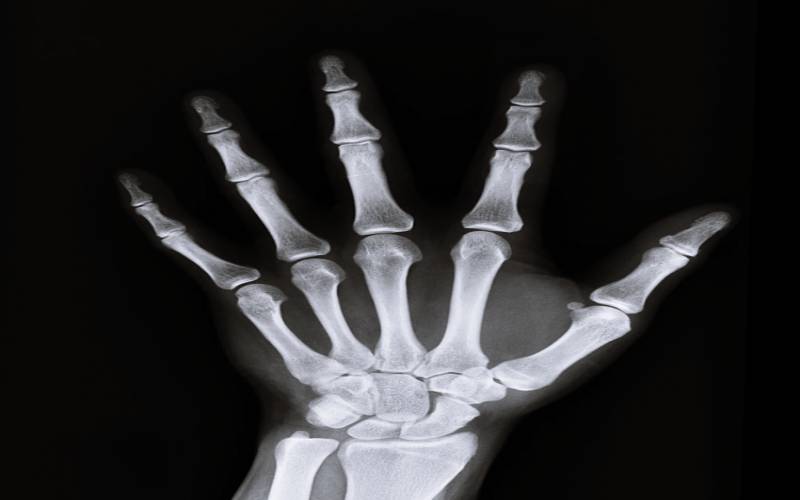

3. 뼈 건강 강화

시서스 효능 중에는 뼈 건강 유지도 있어요. 연구 결과에 의하게 되면 뼈가 만들어지는 것을 담당하는 골세포가 생성되는 것을 자극해주며, 뼈가 부러진 사람들의 치료제로도 활용한다고 해요. 시서스에 들어있는 케토스테론 물질이 뼈를 치유하며, 어르신들의 골다공증, 골절 치료 을 예방하는데도 효과가 있다고 해요.